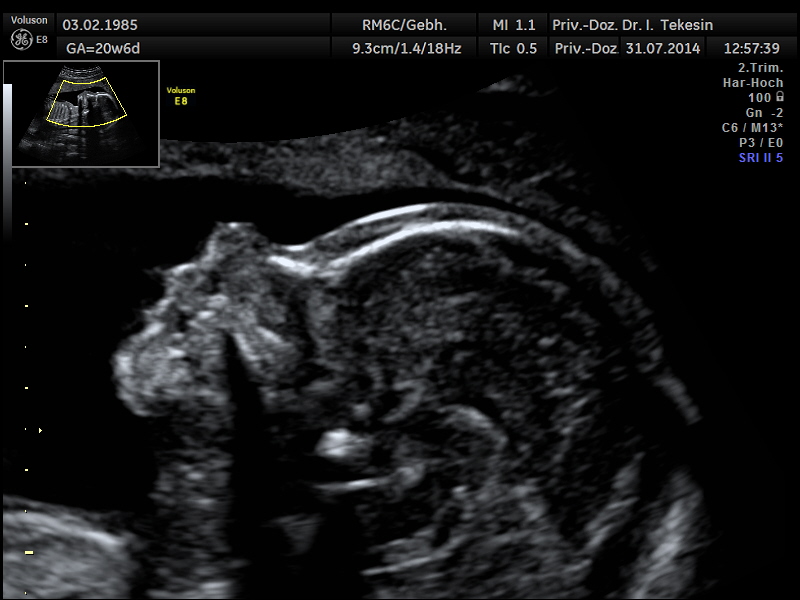

Normaler Vierkammer-Blick mit Farbe

Normales Herz in der 22. Woche